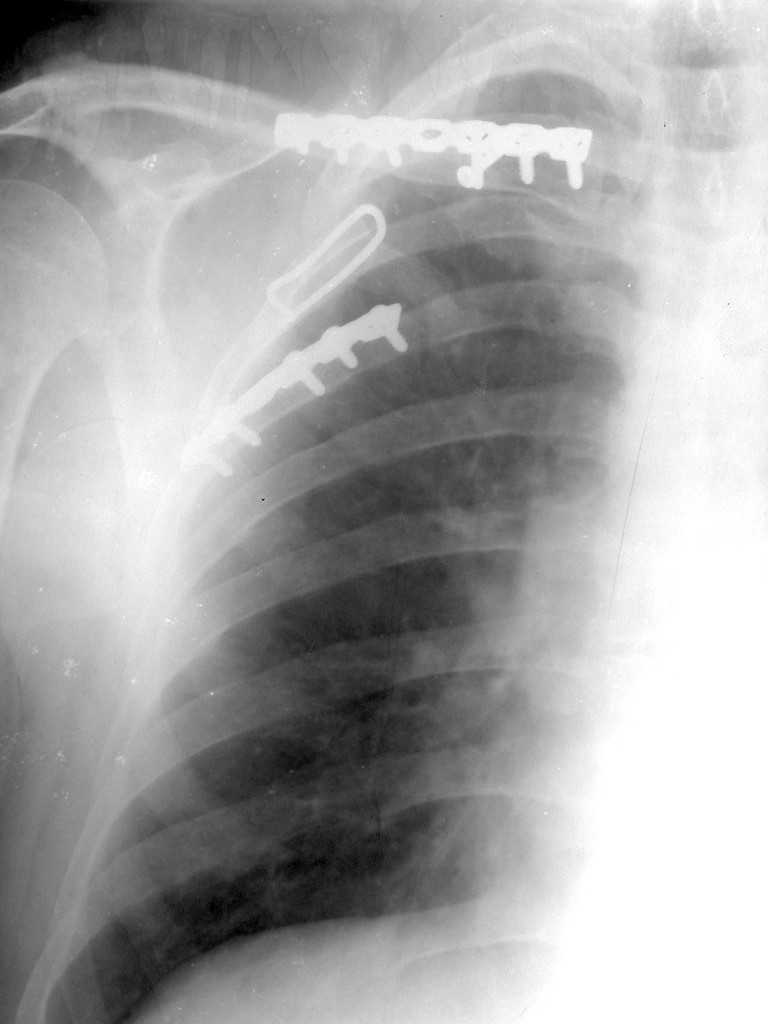

Мы в таких случаях оперируем в 2-а этапа:

1. Стабилизация грудной клетки(фиксируем ребра по одной из линий рекон. LCP)

2. Остеосинтез лопатки из заднего доступа(рекон.LCP, LC-LCP 3,5мм, Т-обр.LCP 3,5мм); ключицу стандартно

К сожелению доктор который занимается грудной клеткой в отпуске, у себя нашёл только вот этот снимок